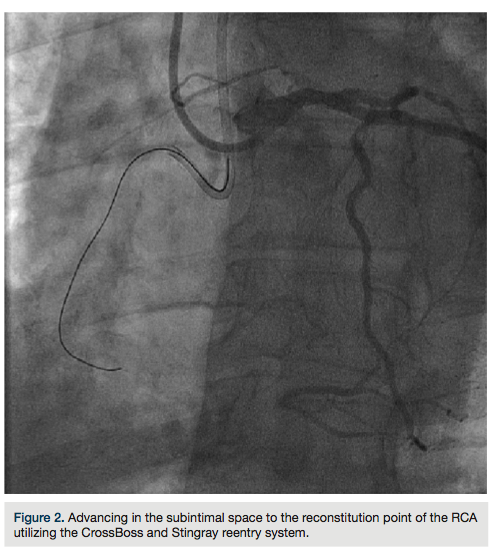

tried to advance a MiracleBros 6 wire (Abbott Vascular) with the over-the-wire balloon; however, that found the false lumen as well. Utilizing the CrossBoss and Stingray reentry system (Boston Scientific), we advanced in the subintimal space to the reconstitution point of the RCA (Figure 2). Contralateral injection demonstrated poor visualization of the distal vessel, likely from antegrade flow (from the subintimal dissection) compressing the vessel (compare distal RCA filling in Figures 1-2). Rather than further extend the dissection plane distally and attempt re-entry, it was decided to proceed with the retrograde approach. After administering additional